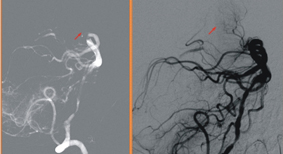

腦幹基底動脈阻塞的患者, 左圖紅色箭頭標示出治療前許多微細血管阻塞無法顯影; 血栓吸出後, 右圖紅色箭頭顯示血流重新恢復的影像。